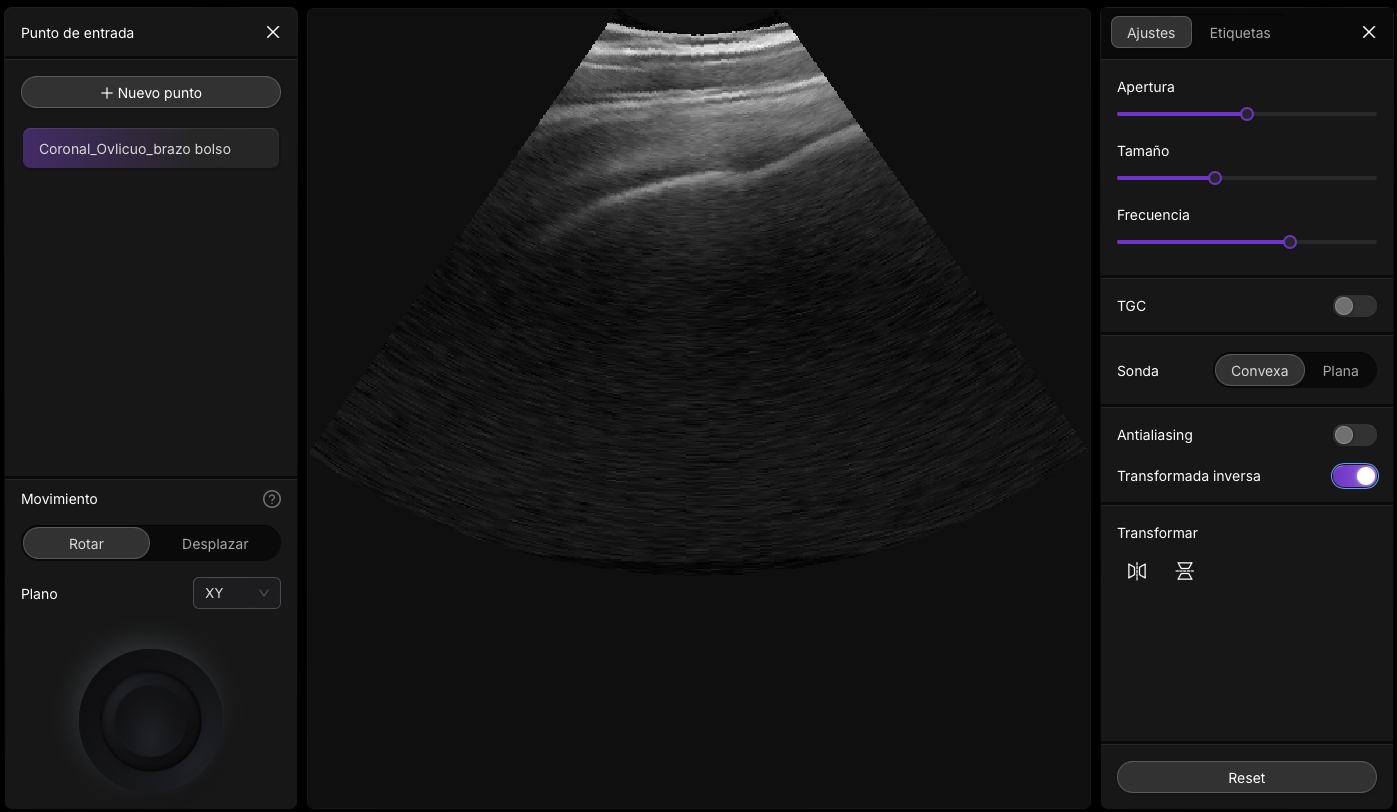

Ir a Imagineus®

Ecografía abdominal mostrando estructura hiperecogénica con sombra acústica

ImageUs 1: Ecografía abdominal en paciente con dispepsia abdominal, donde se aprecia una estructura que muestra una imagen hiperecogenica lineal curvada que genera un artefacto de sombra acustica posterior. Practica con ImagineUS